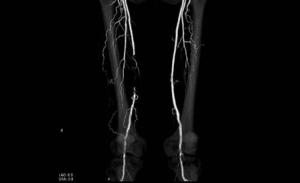

診断には触診などの理学的所見に加えて、足と腕の血圧の比を測定するABI と呼ばれる簡便な検査があります。正常では、ABI は1以上(足の血圧の方が腕の血圧より高い)ですが、血液の流れが悪くなると、ABI は低下します。ABI が0.9以下の場合には、足に動脈硬化が起こっていると考えられます。ABI低下を認めた場合は、専門病院での精密検査になります。一般的には超音波検査、造影剤を使用したCT検査、MRI検査などで確定診断をつけます。